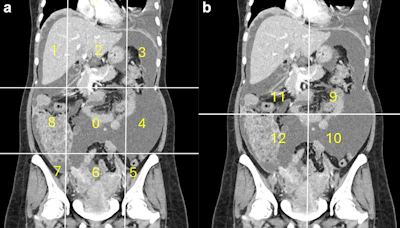

Calculation of radiological peritoneal cancer index (rPCI) adapted from Sugarbaker et al (1). (a) Coronal CT showing regions 0–8. Vertical lines are drawn along the right and left midclavicular line and the horizontal lines along the costal margin and the iliac crests. (b) Coronal CT showing regions 9 to 12. The vertical and the horizontal lines are through the umbilicus divide the small bowel and mesentery into proximal and distal jejunal and ileal regions. Images are republished under a Creative Commons license (CC BY 4.0).